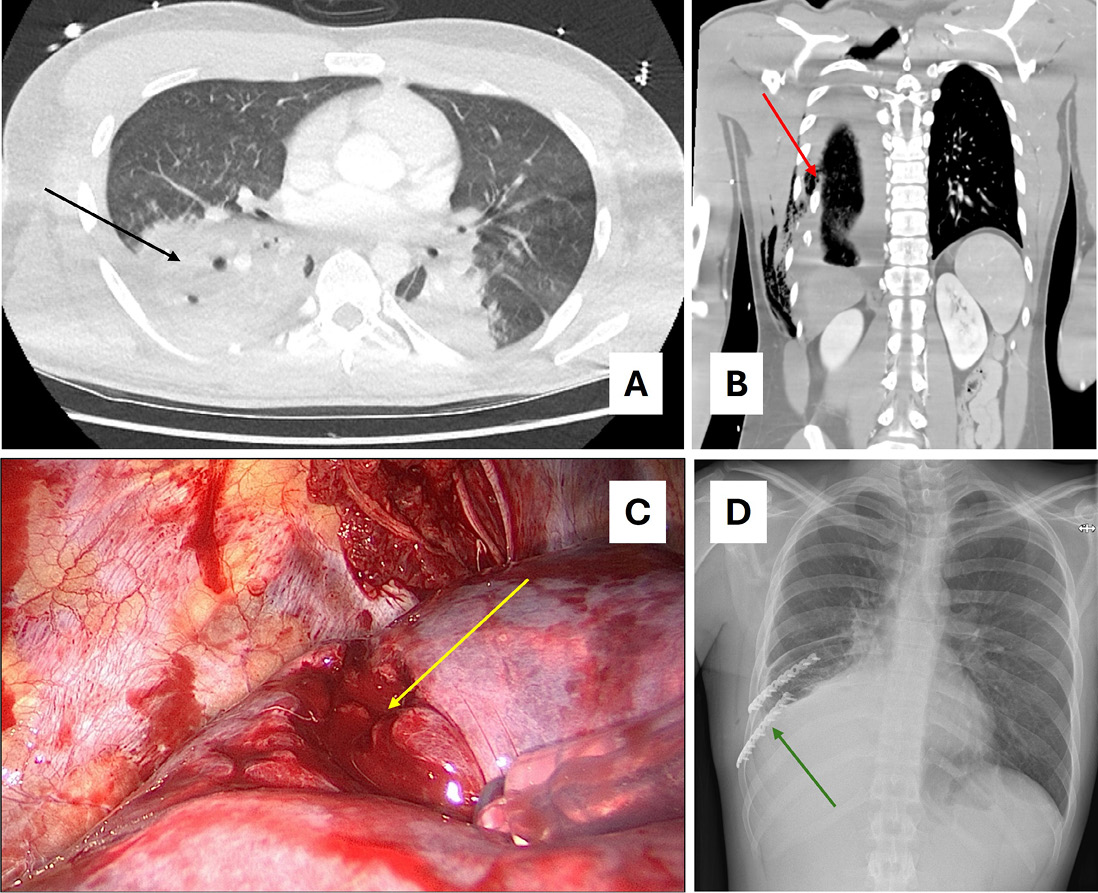

Bei Läsionen der A. subclavia im Bereich des thoracic outlet sollten endovaskuläre oder hybride Verfahren bei geeigneter Anatomie und Ressourcenlage bevorzugt erwogen werden (s. Abb. 2); die Grenzen der Evidenz aufgrund der Seltenheit sind zu berücksichtigen [11, 13, 15].

Abb. 2: Vascular Plug; Vascular Plug der linken A. subclavia bei traumatischem Gefäßabriss. A. Rupturierte A. subclavia (weißer Pfeil). B. Vascular Plug (roter Pfeil). A. subclavia mit liegendem Katheter zur Lage- und Dichtigkeitskontrolle des eingebrachten Vascular Plugs mit Kontrastmittel (schwarzer Pfeil).